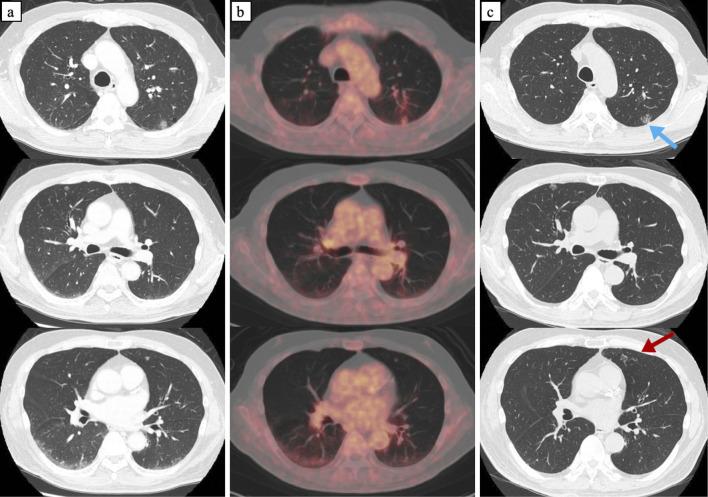

A 74-year-old man with no overt symptoms was referred for a chest computed tomography (CT) that revealed multiple bilaterally pulmonary ground-glass nodules (GGNs) with subtle changes in size over eight months. Surgical lung biopsies were performed in the left upper lobe. A pathologic study confirmed the intravascular large B-cell lymphoma (IVLBCL). This lesion was a nodule-like cluster of atypical cells, meaning that it had been localized for several months. Pulmonary IVLBCL may form focal lesions presenting as GGN on chest CT and progress slowly without apparent symptoms.